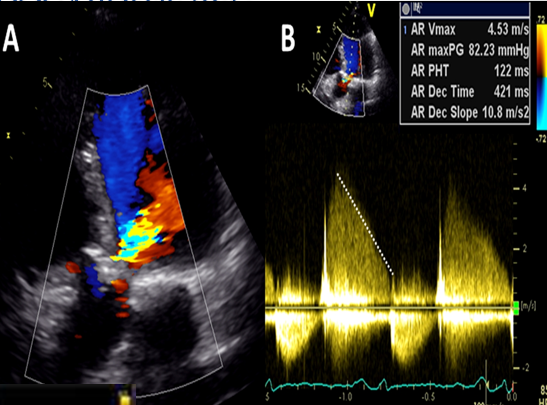

regurg secondary to valvular perforation often have

very steep deceleration slopes